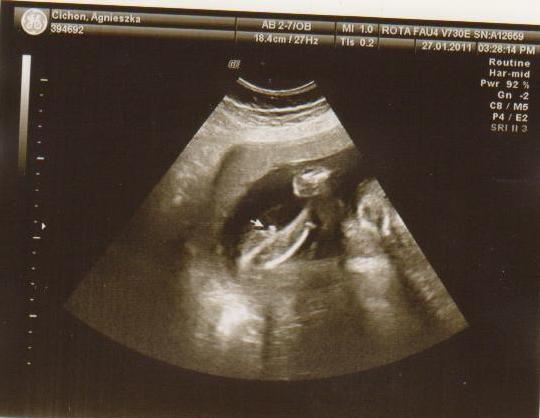

cześć dziewczyny to i ja chciałabym do Was dołączyć, właśnie znalazłam to forum. Mieszkam w Irlandii od 4 lat i mam synka 21 miesięcy, a teraz jestem w 28 tc bliźniaczej :-) dwie dziewczynki dwujajowe :-) też mnie trochę przeraża poród bliźniaków ale trzeba jakoś urodzić ;-) Pierwszy poród miałam jak marzenie szybko, sprawnie i nawet bez znieczulenia, mam nadzieję że i tym razem bęzie podobnie.

Hej podwojne mamunie:-)Ja juz rozpakowana dawno mamusia dubeltowka.Gratuluje wam serdecznie i witam w gronie tych wybranych hihiNiczego sie nie bojcie.Ciaxa blizniacza jest pod specjalna opieka.Czekaja was czeste wizyty w szpitalu i czeste ogladanie maluszkow na usg :-)